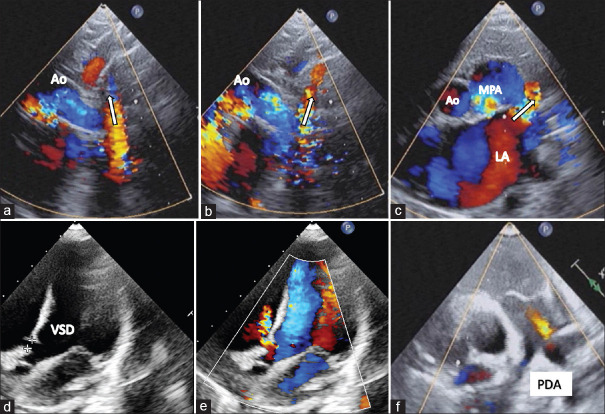

Coronary sinus (CS) defects are rare congenital cardiac anomalies that occur in isolation or with other congenital heart diseases. Persistent left superior vena cava (LSVC) is a relatively common entity that usually drains into the CS, is of no hemodynamic consequence, and is easily diagnosed on echocardiography by a dilated CS and an antegrade flow toward the heart. However, a combination of LSVC and CS defect may reverse its flow direction and CS dilation may be absent. In the absence of echocardiographic clues, the reversed flow can be easily misdiagnosed for other structures such as the more common vertical vein of anomalous pulmonary venous connection or the rarer levoatrial cardinal vein. Here, we report a 2-year-old boy with ventricular septal defect, patent ductus arteriosus, absent CS, and a persistent LSVC with retrograde flow producing a hemodynamically significant pretricuspid left-to-right shunt along with its diagnostic challenges. He underwent successful surgical closure of these defects and had been asymptomatic on follow-up.